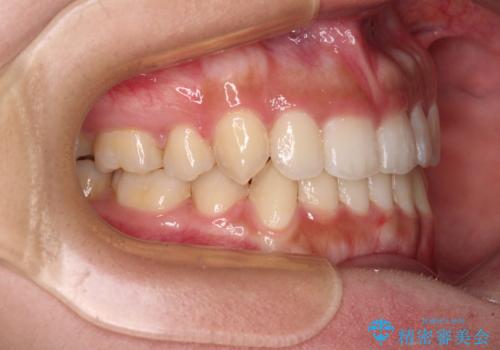

著しい八重歯が気になる インビザラインでの矯正治療

- 4年3ヶ月

ワイヤー装置を用いた場合、一般的には2年程度で終了することを考えると、「移動量が多くなると治療期間が長くなる」というインビザライン矯正の最大の弱点が現れた治療となりました。